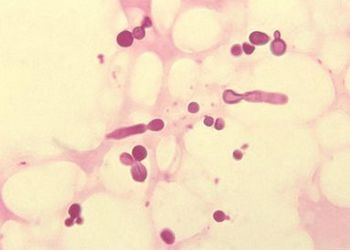

头皮屑在医学上称为头皮糠疹,是一种由马拉色菌(真菌中的一种)引起的皮肤病。马拉色菌在头皮上的大量繁殖引起头皮角质层的过度增生,从而促使角质层细胞以白色或灰色鳞屑的形式异常脱落,这种脱落的鳞屑即为头皮屑。头屑产生的原因通常分为生理性和病理性。

5.有一种头癣也可以引起头屑的增多,主要是白癣,同时会伴有脱发,真菌学检查阳性,诊断比较容易。